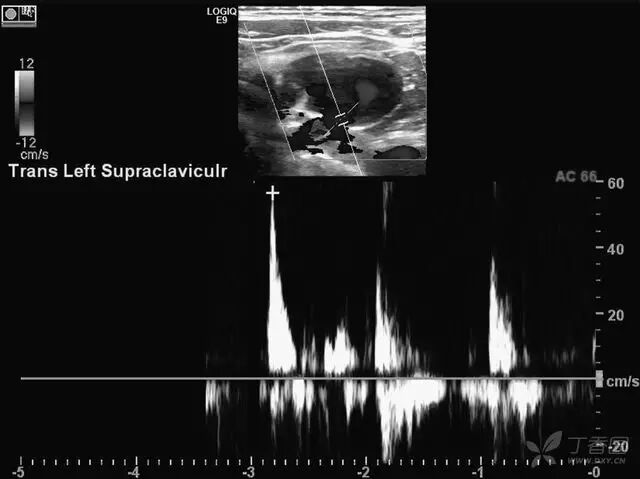

图 3  横断面频谱多普勒声像图显示病灶内有 2 处与静脉交通(仅显示 1 处),可见双向静脉血流频谱,肿物未与动脉直接交通,但频谱波形提示可能受左上肢动静脉瘘影响